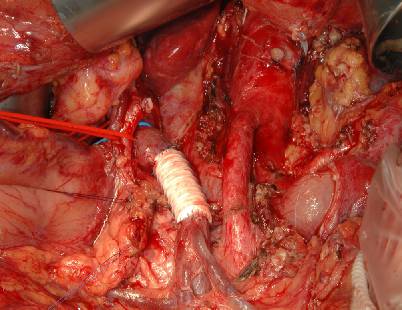

Abb. 3

Intraoperativer Situs nach einer subtotalen Pankreaslinksresektion mit Ersatz der V. mesenterica superior durch eine Goretex®-Ringprothese

Abb. 4

Intraoperativer Situs nach einer Whippl’schen Operation mit Ersatz der V. mesenterica superior durch eine Goretex®-Ringprothese